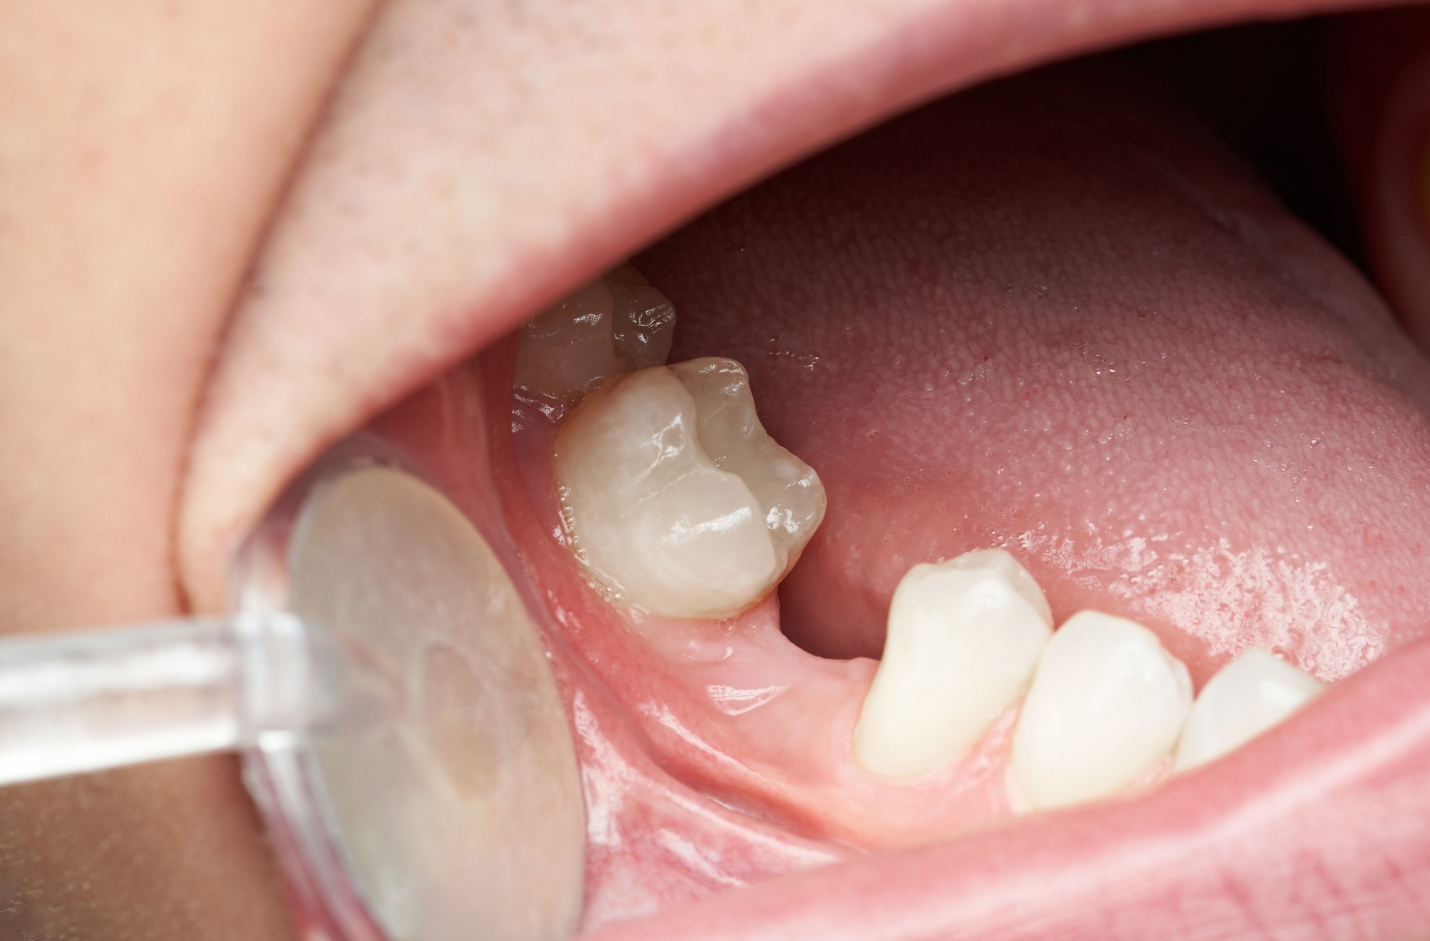

Dental implants replicate the structure of natural tooth roots. Each implant consists of a small titanium post surgically placed into the jawbone. Over the next few months, the bone grows and fuses around the post in a process called osseointegration.

This fusion allows the implant to function just like a natural root, delivering the same kind of mechanical stimulation needed to maintain bone density. As a result, implants effectively halt bone loss and help preserve the strength and volume of the jaw.